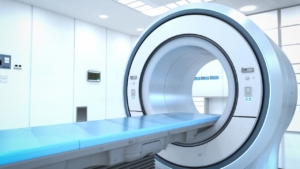

Managing Contrast Media Allergic Reactions: Emergency Protocols For Imaging Staff

Key Takeaways Contrast-enhanced imaging has become indispensable for accurate diagnosis across radiology departments nationwide. While these procedures are generally safe,